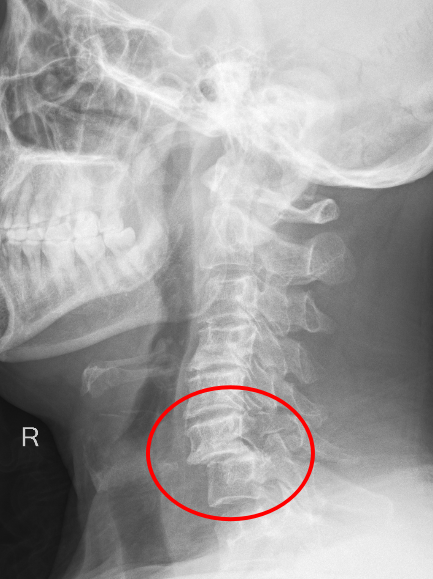

近日,重庆医科大学附属璧山医院(重庆市璧山区人民医院)骨科团队凭借精湛技术和默契协作,成功为一名高空坠落致颈椎重创的危重患者实施了高难度复位固定手术,术后患者恢复良好。

近日,重庆医科大学附属璧山医院(重庆市璧山区人民医院)神经外科成功为一名遭遇严重寰椎骨折的患者施行了高难度的后入路寰椎骨折复位内固定术以及枕颈融合植骨固定术,术后随访显示,患者恢复状况良好,拥抱健康新生活。